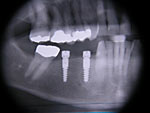

Die folgenden Patientenfälle sollen Ihnen einen Einblick in die Möglichkeiten der modernen Implantation geben.

Kurzimplantate und Sofort – Implantate: